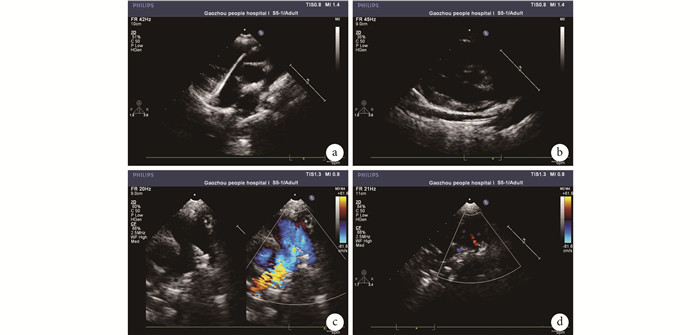

儀器選擇飛利普 IE33 床旁超聲診斷儀器。首先于胸骨旁多切面觀察 ASD、PDA 位置及大小,再次確定適應證。所有入選患者均由熟悉介入的外科醫生和超聲醫師在導管室或手術室進行。患者取仰臥位,局部麻醉或全身麻醉。于患者臍部以下、膝蓋以上消毒鋪單,臍部以上裸露方便超聲醫師檢查。術者及助手位于患者右側,超聲醫師位于患者右側操作。穿刺右側股靜脈,經動脈鞘送入導管及導絲。PDA 封堵(圖 1):超聲觀察導管和導絲走行于下腔靜脈并進入右房。使導管指向三尖瓣,置入超滑導絲,在超聲引導下通過三尖瓣、右室、肺動脈、動脈導管未閉到達降主動脈,交換為加硬導絲,置入輸送鞘管到達降主動脈,封堵器腰部直徑要選擇比 PDA 最窄處內徑大 3~6 mm,在超聲監測下釋放封堵器。ASD 封堵(圖 2):探頭選擇胸骨旁四腔心切面,在超聲引導下從股靜脈置入加硬導絲和輸送鞘管,將鞘管通過 ASD,撤出導絲和內芯后超聲可看到鞘管有“雙腔征”,然后置入 ASD 封堵器(腰部直徑比 ASD 最窄處內徑大 2~4 mm),依次打開左右盤傘封堵 ASD。行多切面觀察,觀察封堵器的位置、形態和周圍結構,然后指導操作醫師釋放封堵器,確定封堵成功。ASD 患者均于術后 24 h 皮下注射低分子肝素抗凝,每日口服阿司匹林 3~5 mg/kg 抗凝 6 個月。PDA 患者不需要抗凝。